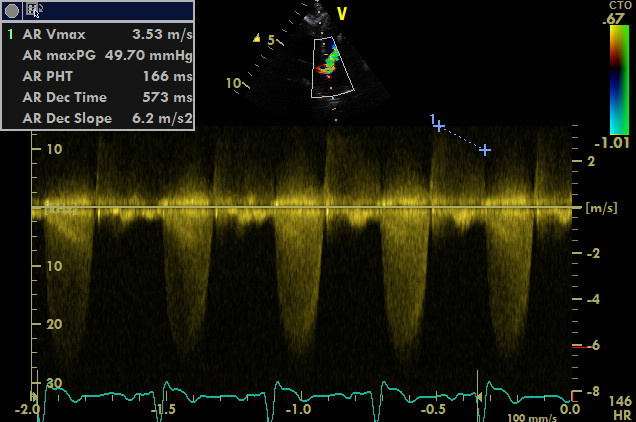

come si puo’ notare dai particolari nelle immagini zoom la struttura valvolare appare integra con una normale conformazione delle cuspidi la turbolenza e’ generata da una piccola banda fibrosa sottovalvolare ,in questo caso a dispetto delle alterazioni minime visualizzabili nell’esame B mode la stenosi sulla base del gradiente appare severa ,il PHT inferiore ai 300mm/sec dell’insufficienza aortica che quasi sempre accompagna la stenosi indica pressioni diastoliche nel ventricolo sx elevate